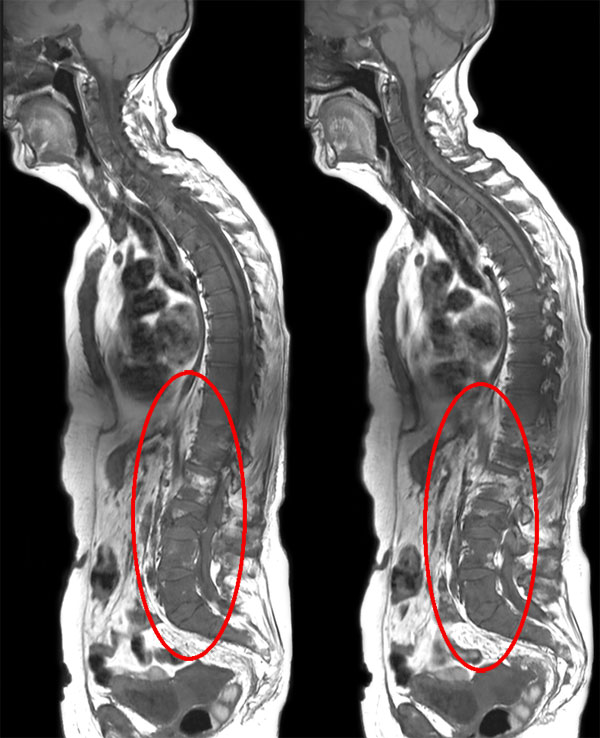

Patient with bone lesions.